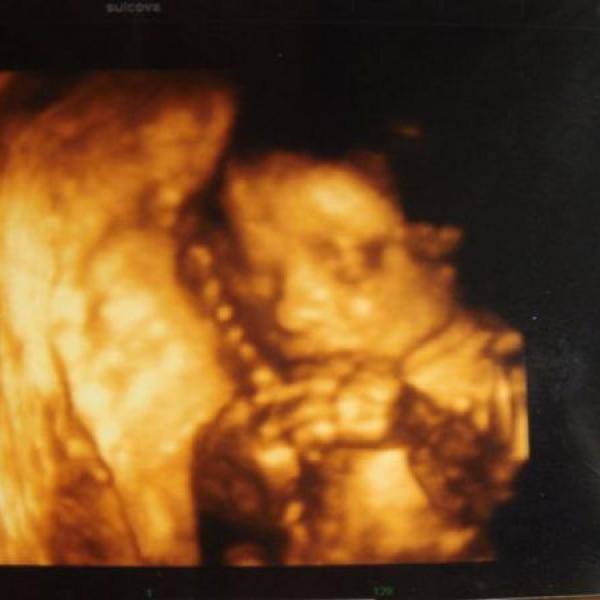

Ahojky holky....malá se nepřetočila....asi už se nepřetočí takže víme nástup na císaře.......30.12.